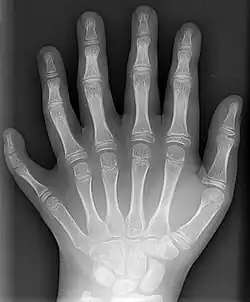

Diagnosis

Classification is performed by using x-ray imaging to see the bone structures.[17] In 1961, Frantz and O'Rahilly proposed that congenital anomalies of the limb could be classified in seven categories, based on the embryonic failure causing the clinical presentation. These categories are failure of formation of parts, failure of differentiation, duplication, overgrowth, undergrowth, congenital constriction band syndrome, and generalized skeletal abnormalities.[36] In 1976 this was modified by Swanson.[37] Polydactyly belongs to the category of duplication.[12] As of 2009, research has shown that the majority of congenital anomalies occur during the 4-week embryologic period of rapid limb development.[12]